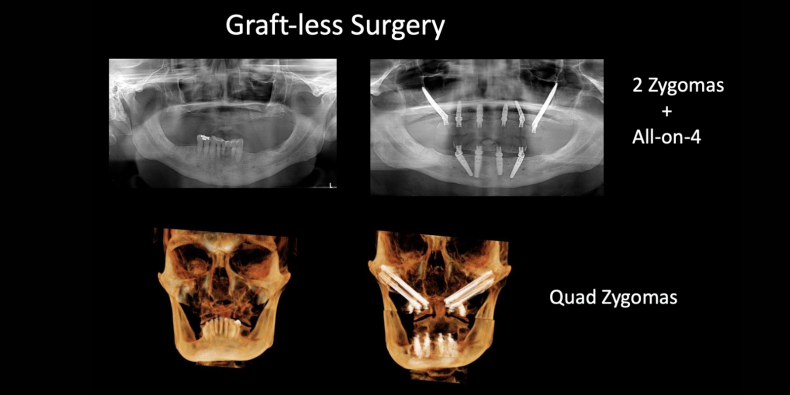

Examples of Zygomatic Implants:

Case #1:

One Zygomatic Implant per side, 4 additional implants in upper jaw

All-on-4 on lower jaw

Case #2